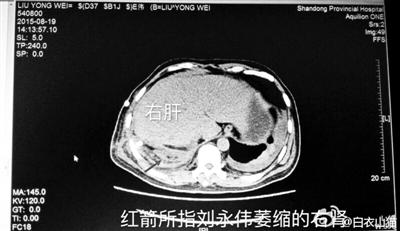

刘永伟的医学影像

针对刘永伟“右肾缺失”,南京军区总医院检查报告显示:肝脏内后方与右侧膈脚间软组织影,考虑为外伤后右肾移位、变形、萎缩,其外侧软组织感染、窦道形成。专家组讨论意见为:患者胸腹部多脏器严重复合伤,多发性肋骨骨折,外伤性膈肌破裂,肝脏、右侧肾脏疝入胸腔,右侧肾脏挫裂伤、肝脏挫裂伤。术后第一天胸腹部CT、第五天腹部CT提示右肾存在并可见裂伤。